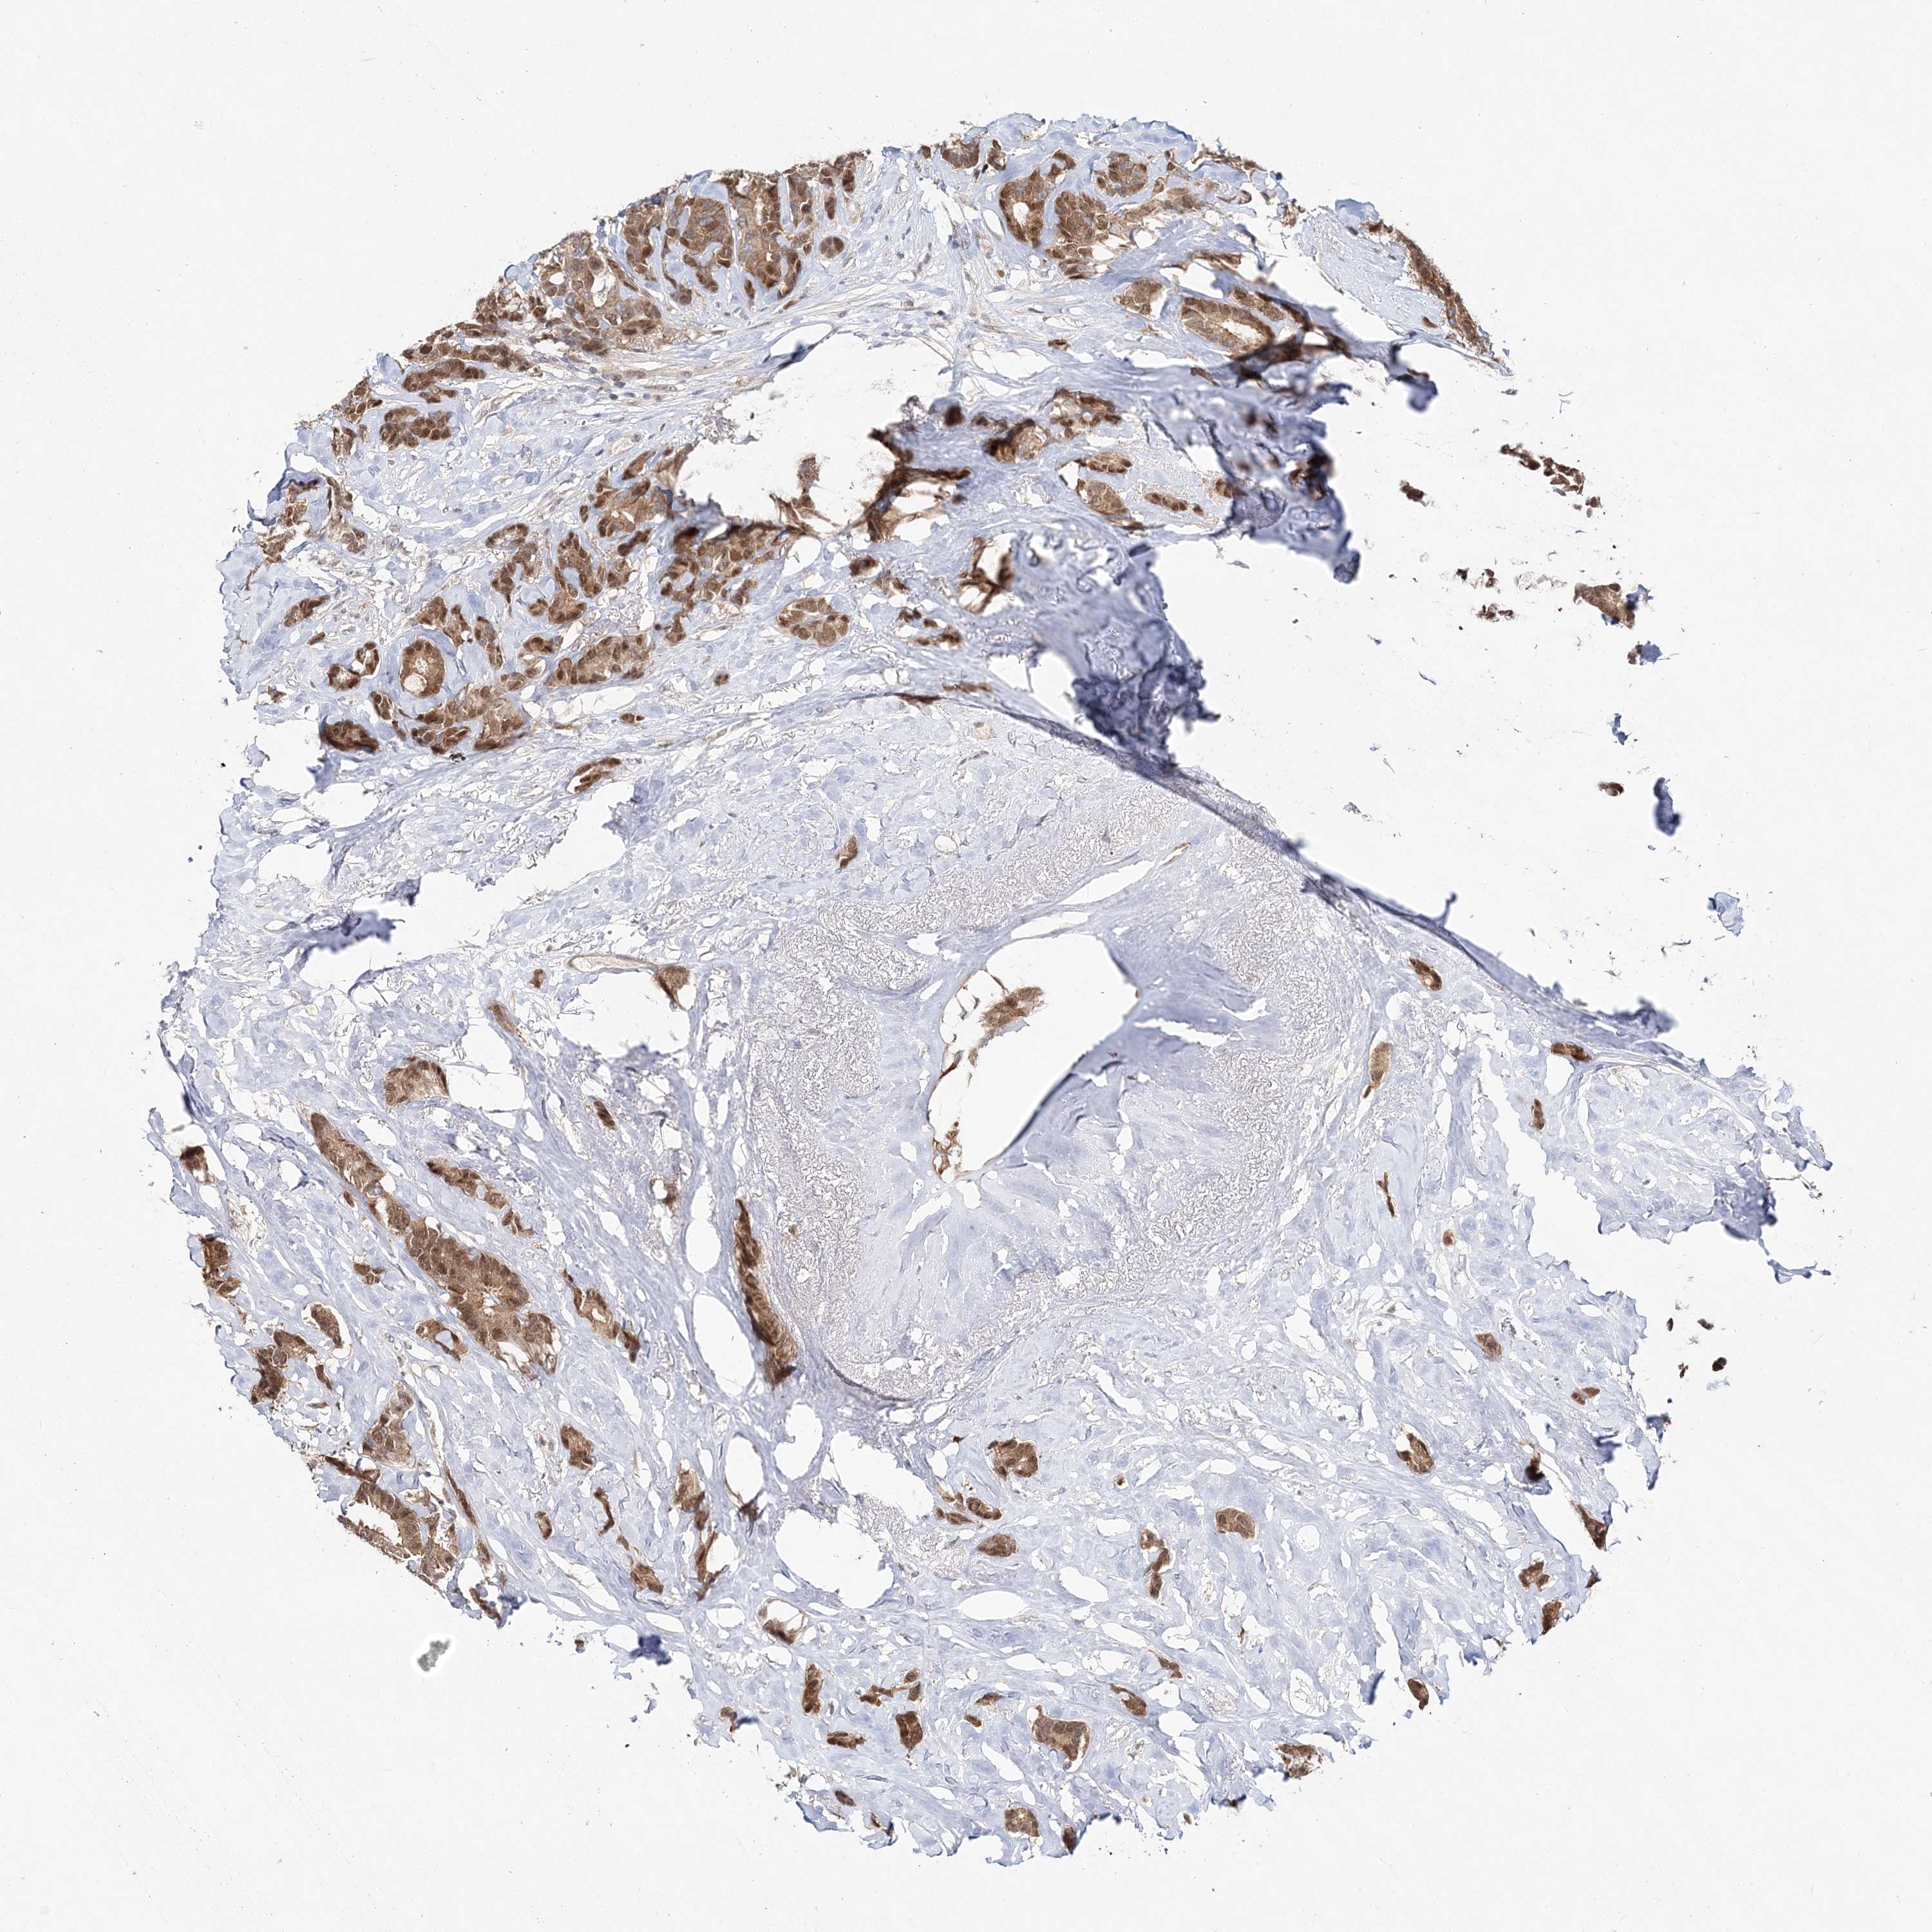

CANCER BREAST CANCER Show tissue menu

BRCA TCGA BRCA VALIDATION PROTEIN EXPRESSION